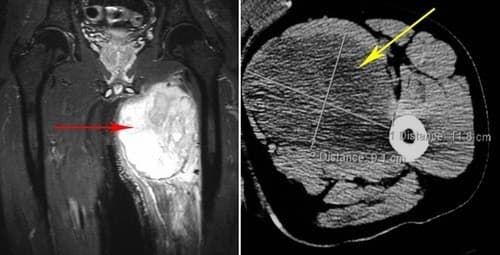

Để quan sát các hình ảnh ung thư mô mềm người bệnh cần tiến hành chụp CT hoặc chụp MRI. Những phương pháp chẩn đoán này còn giúp xác định vị trí, kích thước và mức độ xâm lấn của bệnh.